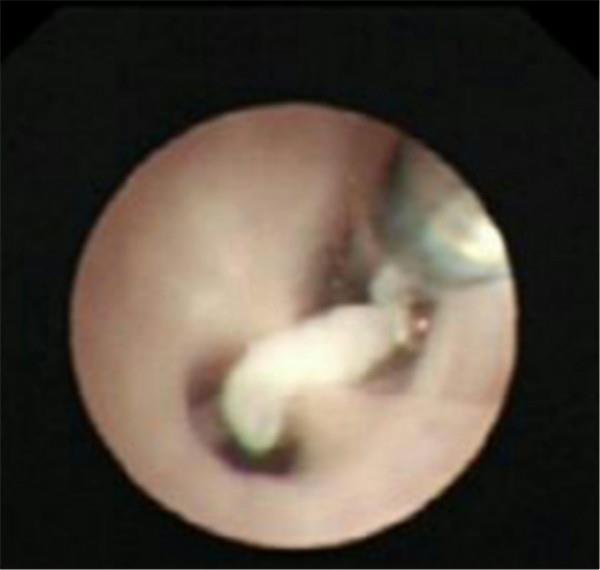

檢查中氣道內(nèi)情景

肺泡內(nèi)灌洗出來(lái)的渾濁液體

塑形

嗆入氣道的瓜子